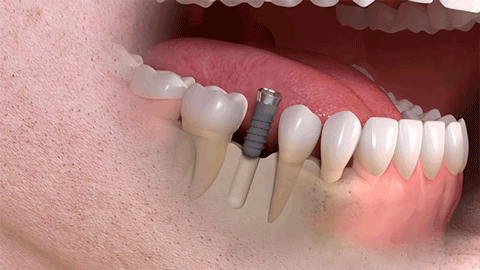

單顆牙種植

相比傳統(tǒng)固定義齒和活動(dòng)義齒,種植牙是醫(yī)學(xué)界公認(rèn)的理想修復(fù)方式,被譽(yù)為“人類的第三副牙”。相比活動(dòng)假牙不舒服、難清洗、容易引起口腔黏膜病變,種植牙更穩(wěn)固耐用,舒適美觀,咀嚼功能好,一次種植,即可重獲好口福!種植牙不僅是中老年人的專利,年輕人因意外、牙病等造成的單顆、多顆牙齒缺失,也能夠通過種植牙進(jìn)行修復(fù)調(diào)節(jié),重獲幸福笑容。